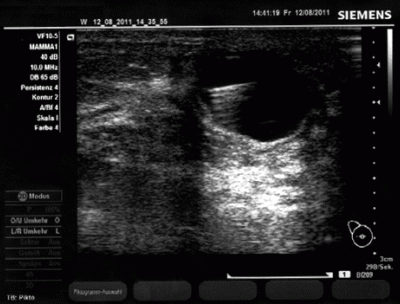

Mammazyste vor der Punktion